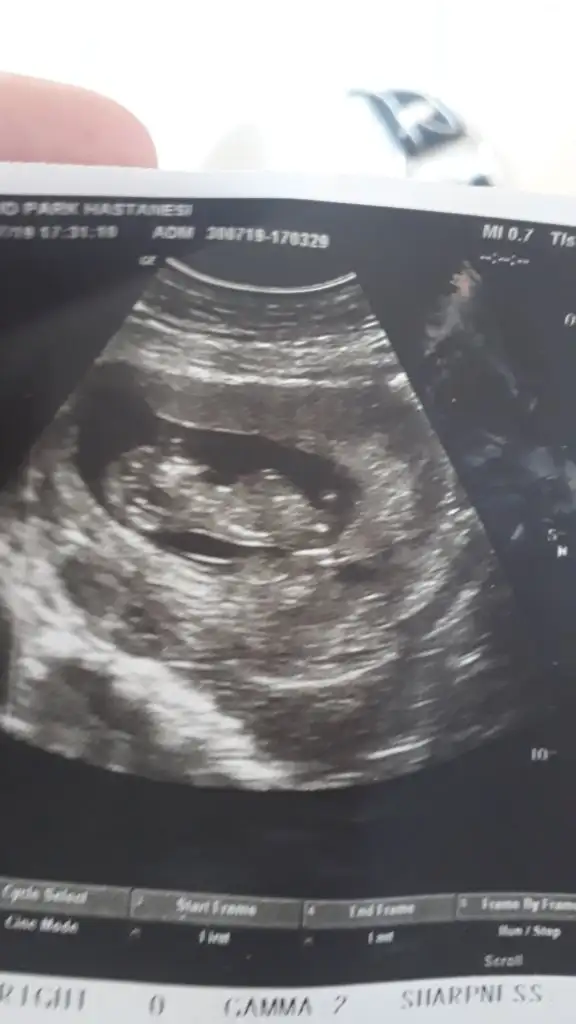

Tamam kız bu bebiş.kesin kızEki Görüntüle 2294615 Eki Görüntüle 2294617

Bunlarda az önce alınan resimler normalde 11 hafta 6 günlük ama usg de 12 hafta 6 günlük